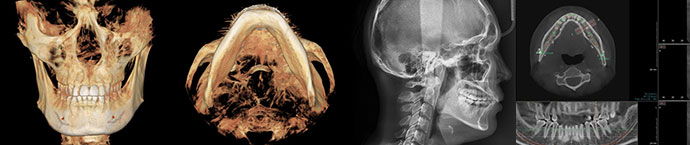

At View Plastic Surgery, double jaw surgery is conducted using the 3D-CT Viewer, allowing

precise analysis of teeth, bones, facial symmetry, jaw-to-teeth proportions, occlusion, and

soft tissues. Additionally, the Morpheus 3D system scans the face and creates a 3D virtual

simulation, enabling a preview of post-surgery changes. This ensures a detailed 1:1 customized

surgical plan and results in a highly refined surgical outcome.

Using advanced diagnostic systems such

as 3D-CT and X-RAY, double jaw surgery

accurately analyzes teeth, bones,

facial balance, jaw-to-teeth proportions,

and soft tissues. Additionally, the Morpheus

3D system scans the face and provides

a 3D virtual simulation, allowing patients to

predict post-surgery outcomes.

View Plastic Surgery utilizes high-resolution diagnostic tools like 3D-CT,

X-RAY, and Morpheus to precisely analyze facial asymmetry, dental occlusion,

and bone structure, creating personalized surgical plans for ideal aesthetic

and functional results.

Using high-resolution diagnostic tools like 3D-CT,

X-RAY, and Morpheus, we carefully analyze each

individual's facial features, dental occlusion, bone

structure and size, nerve line positions, and soft

tissue to create a precise surgical plan.